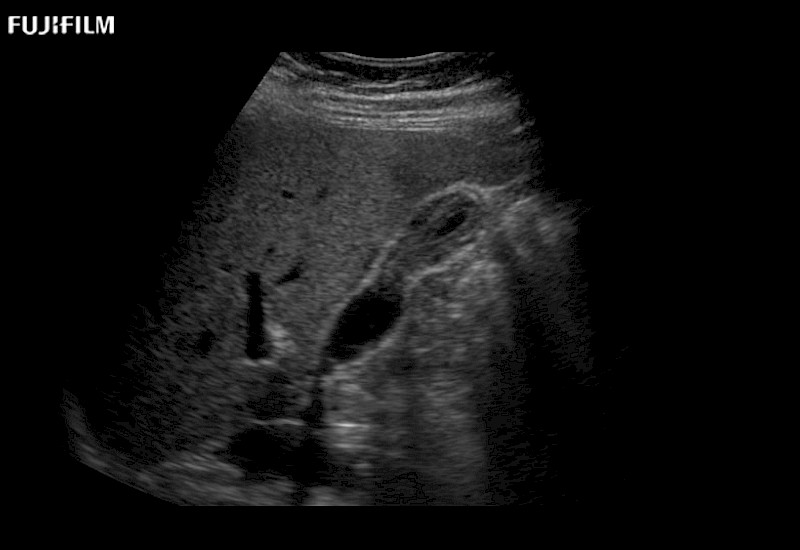

Exclusive linear array rigid laparoscopic transducer for better visualization of targeted lesions.

Main Specifications:

Exclusive linear array robotic surgery transducer.

Features: